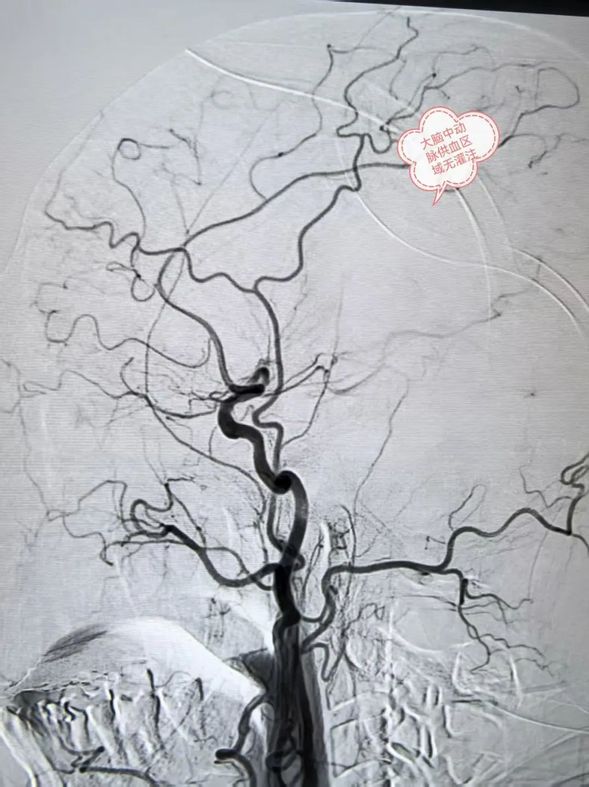

术前大脑中动脉闭塞,供血区域无灌注